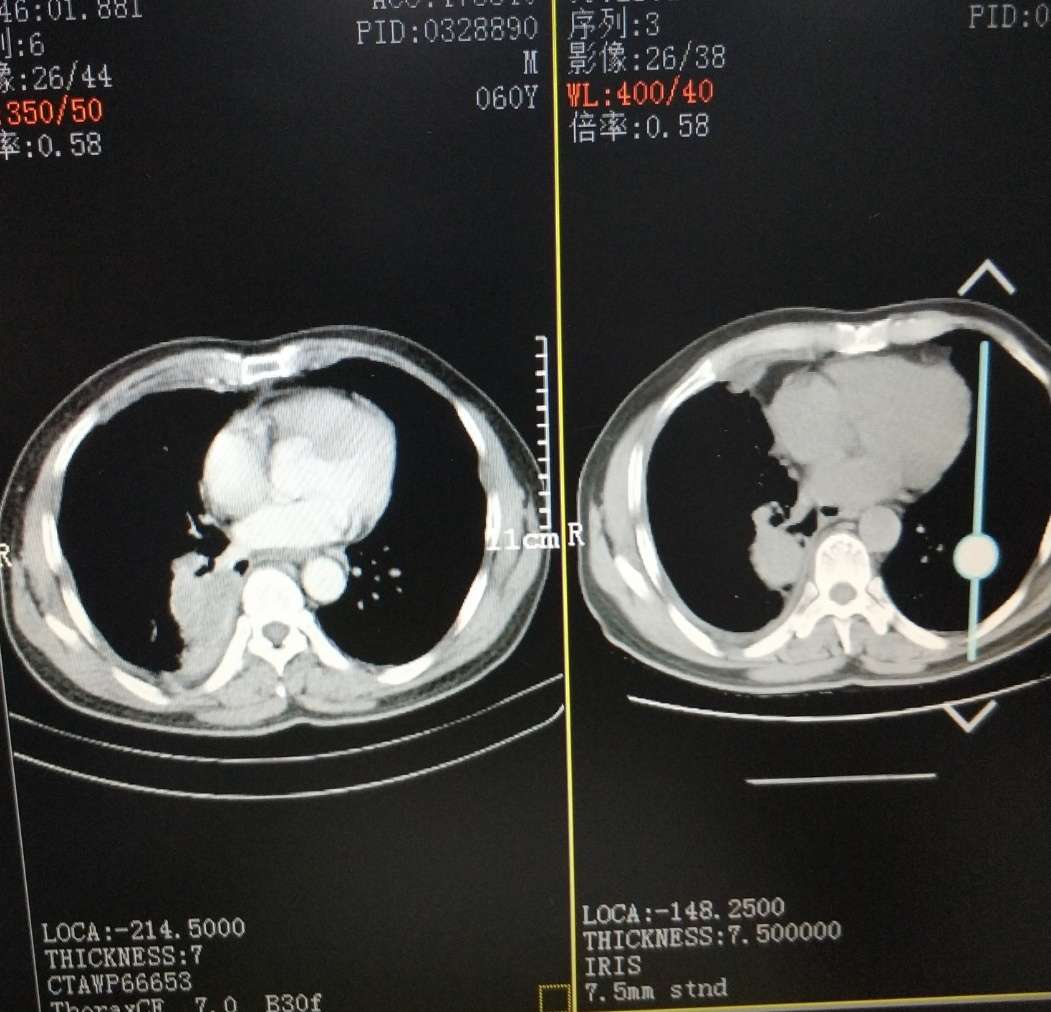

ct为前后吃易瑞沙一个月对比

易瑞沙前后一个月对比

一个月对比,现在的问题是胸水反反复复易瑞沙控制不了胸水,医生说效果不怎么好